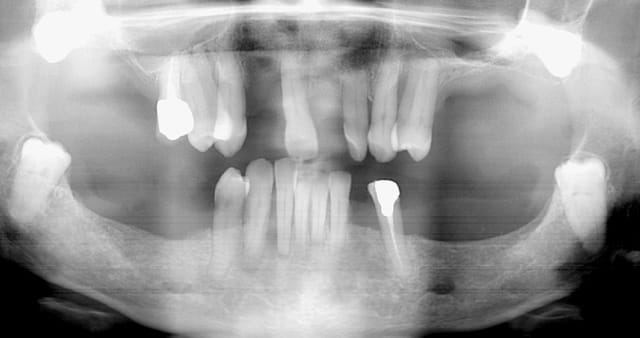

nouveau patient, il en a assez de son complet sup et de son édentation mandibulaire (le stellite est dans un tiroir depuis 15 ans).

Il veut vraiment une solution fixe.

je vous avoue que ce qui me pose le plus problème c'est son occlusion. Sous le complet, à la palpation on ne sent pas une crête très résorbée (mais la palpation est parfois (souvent) trompeuse). Le patient me dit que lorsqu'il avait encore ses dents en haut elles étaient en "bout à bout" avec les incisives inf. Il ne possède pas un profil cutané typique des classes III squelettique. J'ai vérifié s'il ne propulsait pas en fermant: négatif. Il semble donc qu'une résorption centripète progressive ait eu lieu au niveau de son maxillaire aboutissant à l'état actuel. je vais faire une téléradiographie de profil pour préciser la classe squelettique.

Si vraiment la résorption maxillaire est modérée, je pourrais prévoir une greffe d'apposition au niveau prémaxillaire (prélèvement symphysaire par exemple) et 2 sinus-lifts. En revanche si le recul maxillaire est plus marqué il serait peut être judicieux d'envisager alors une chirugie d'avancée du maxillaire.

la canine incluse sera extraite et la zone pourra être reconstruite par greffe lors de la chirurgie dans l'une ou l'autre des solutions.

pour la mandibule: assainissement parodontal (les 41 31 ne sont pas mobiles actuellement). La résorption osseuse est importante horizontalement et verticalement, on aurait un rapport couronne/implant très défavorable sans redonner de la hauteur à la crête. Alors comment reconstruire ici: greffes en onlay? (où prélever suffisament d'os?), ROG avec de l'os autogène et membranes gore tex renforcées titane?

ou alors, plus simple, extraction de toutes les dents, 6 implants et une prothèse transvissée avec MCI et en haut du "all on six"?

quoiqu'il en soit pour prendre une décision il me faut préciser la classe squelettique et les résorptions osseuses. Je vais donc faire un montage haut et bas (avec les incisives en bout à bout) avec un matériau radiopaque et faire pratiquer une téléradiographie de profil et des tomographies de l'ensemble des maxillaires.